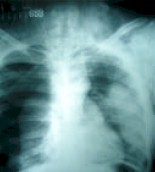

Figura 1: Se observa lesión pulmonar con zona radio opaca en lóbulo medio del pulmón izquierdo (hematoma) y ausencia de parénquima pulmonar en hemitórax derecho (signo del pulmón caído).